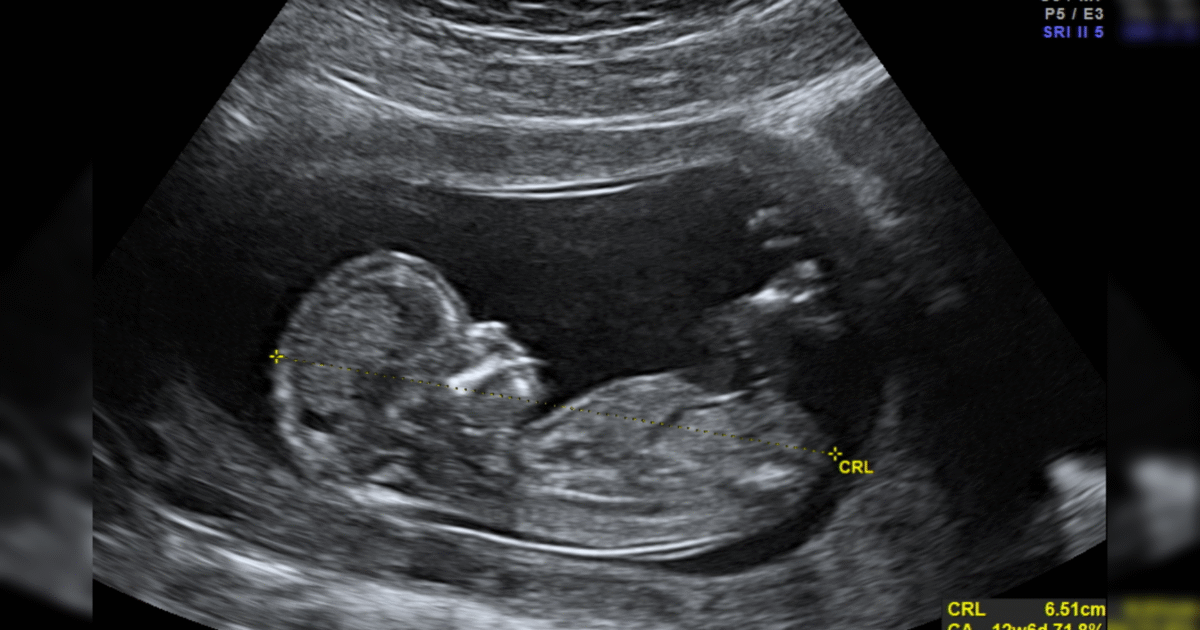

Others are ordering pills to abort babies way beyond 10 weeks’ gestation, like a horrific case from Nebraska that had a mother and daughter talking on Facebook Messenger about the third-trimester baby they aborted with pills at 29 weeks, then burned and buried in the back yard.